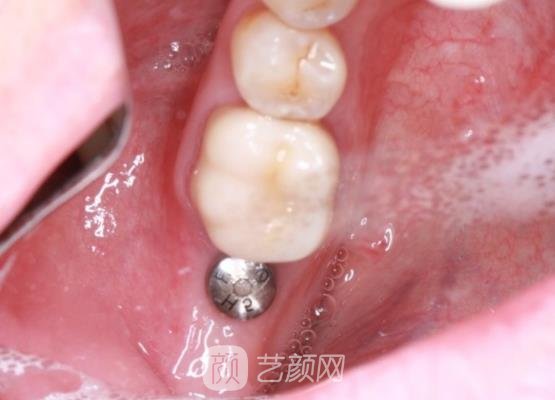

手术刚结束,我的牙龈处还有一些肿胀的情况,而且还有一些疼,医生告诉我这些情况比较正常,如果几天以后还是有着疼痛的情况,就让我来找他,进行复查。

医生还叮嘱了我一些术后的注意事项,告诉我术后当天尽量不要漱口,防止对口腔的伤口造成感染,延长手术的恢复期,这段时间也不要吃一些坚硬的食物,防止造成种植牙的松动。

几个月以后,我的种植牙已经恢复好了,这个时候也不需要注意什么饮食问题了,终于可以大吃特吃了,可以看到我的真的很自然,基本上看不到人工手术的痕迹,就像是我自己的牙齿一样,果然手术还是有成果的,让我很满意。